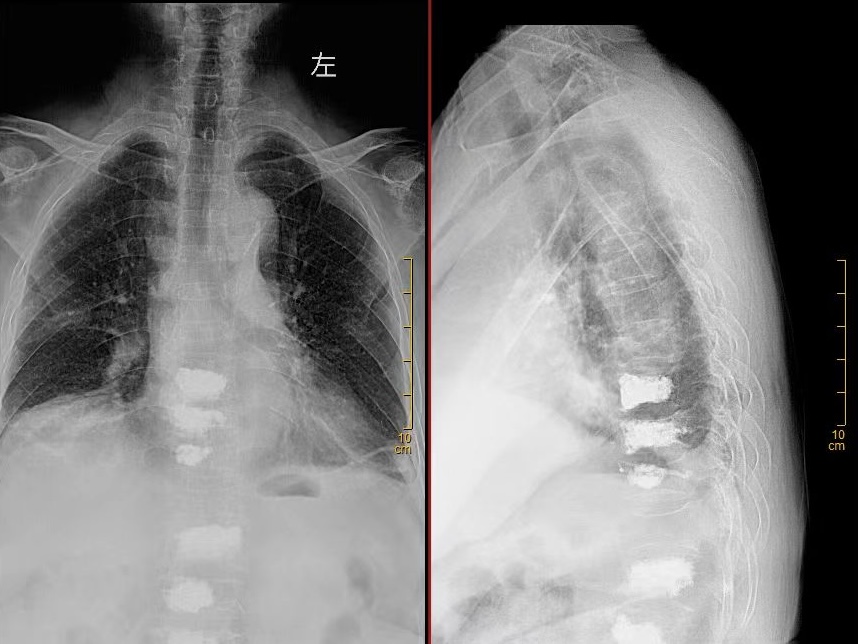

术前DR

“做完手术就能下床走路,真是太感谢你们了!” 近日,在我院骨一科病房,赵奶奶握着医护人员的手,激动地说道。赵奶奶是一位重度骨质疏松患者,近年来饱受腰背疼痛的折磨,曾多次来我院接受骨水泥治疗。近日,赵奶奶不慎闪腰,导致胸背部剧烈疼痛,难以忍受,遂来我院骨一科就诊。经检查,赵奶奶被诊断为胸7椎体压缩性骨折。